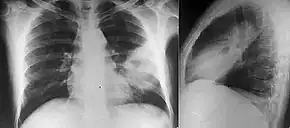

People with diabetes mellitus or regular exposure to the bacteria are at increased risk of developing melioidosis. The disease should be considered in those staying in endemic areas who develop fever, pneumonia, or abscesses in their liver, spleen, prostate, or parotid glands.[2] The clinical manifestation of the disease can range from simple skin changes to severe organ problems.[2] Skin changes can be nonspecific abscesses or ulcerations.[9] In northern Australia, 60% of the infected children presented with only skin lesions, while 20% presented with pneumonia.[4] The commonest organs affected are liver, spleen, lungs, prostate, and kidneys. Among the most common clinical signs are presence of bacteria in blood (in 40 to 60% of cases), pneumonia (50%), and septic shock (20%).[2] People with only pneumonia may have a prominent cough with sputum and shortness of breath. However, those with septic shock together with pneumonia may have minimal coughing.[3] Results of a chest X-ray can range from diffuse nodular infiltrates in those with septic shock to progressive solidification of the lungs in the upper lobes for those with pneumonia only. Excess fluid in the pleural cavity and gathering of pus within a cavity are more common for melioidosis affecting lower lobes of the lungs.[3] In 10% of cases, people develop secondary pneumonia caused by other bacteria after the primary infection.[4]

Various imaging modalities can also help with the diagnosis of melioidosis. In acute melioidosis with the spreading of the bacteria through the bloodstream, the chest X-ray shows multifocal nodular lesions. It may also show merging nodules or cavitations. For those with acute melioidosis without the spread to the bloodstream, chest X-ray shows upper-lobe consolidation or cavitations. In chronic melioidosis, the slow progression of upper-lobe consolidation of the lungs resembles tuberculosis. For abscesses located in other parts of the body apart from the lungs, especially in the liver and spleen, CT scan has higher sensitivity when compared with an ultrasound scan. In liver and splenic abscesses, an ultrasound scan shows "target-like" lesions, while CT scan shows "honeycomb sign" in liver abscesses. For melioidosis involving the brain, MRI has higher sensitivity than a CT scan in diagnosing the lesion. MRI shows ring-enhancing lesions for brain melioidosis.[10]